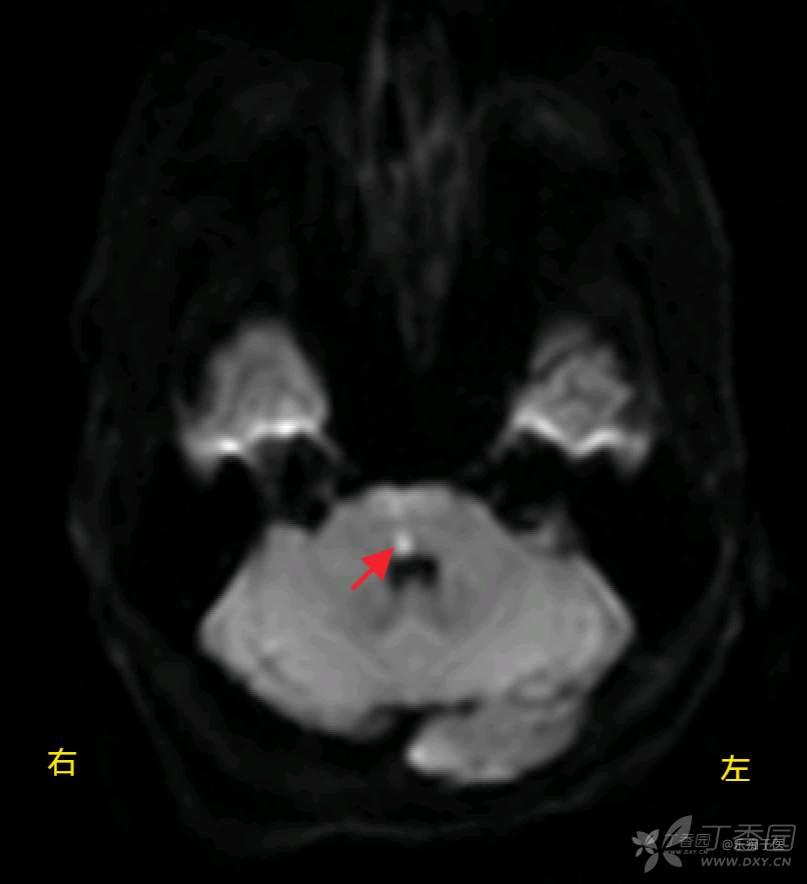

辅助检查:颅脑MRI:右侧桥脑斑点状新鲜脑梗死灶,胼胝体膝部脑软化灶。CTA提示:左侧大脑后动脉P2段重度狭窄。DSA未见明显异常。

DWI